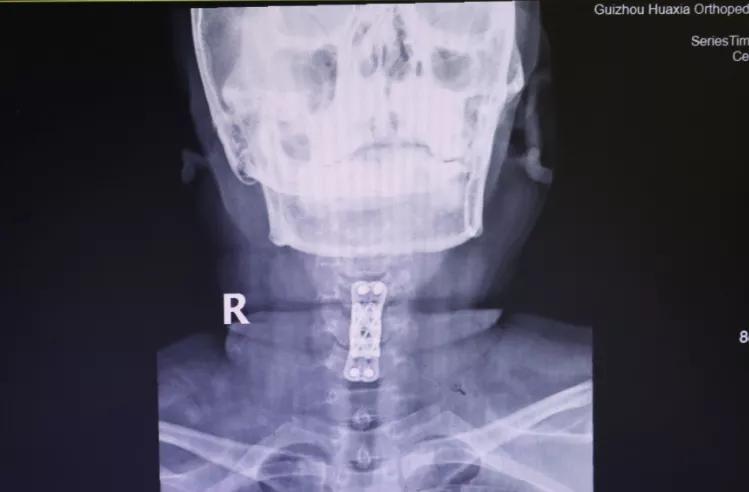

做了全面的检查后,胡阿姨被诊断为:颈椎病(脊髓型);颈椎间盘突出症 ;颈椎后纵带骨化症;肝功能不全 。患者诊断明确,存在明显手术指征,需行手术治疗,进行椎管减压,神经根松解,以阻止病变进一步发展,防止出现更加严重的双下肢瘫痪或大、小便功能障碍。

面对患者严重的病情,为使患者得到最佳、最快的治疗,12月18日,完善术前检查后,为胡阿姨实施了手术治疗。术后,疼痛、麻木等症状大大减轻。